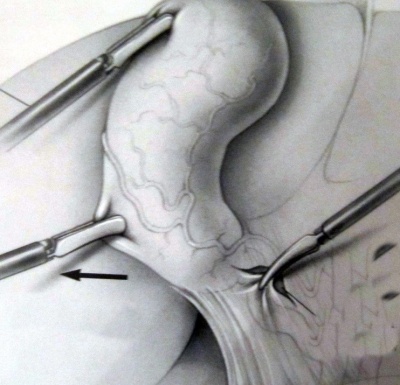

כעת יש לפתוח את הצפק בבסיס כיס המרה ולחשוף את צינור המרה ואת עורק המרירה (איור 10.8). בעזרת מכלב יש "לקשור" את עורק כיס המרה ואת צינור כיס המרה ולנתקם.

| איור 10.8: חשיפת הציסטיקוס (תמונה עליונה) וסגירת צינור כיס המרה על-ידי מכלב (תמונה תחתונה). |

יש המבצעים בשלב זיהוי הצינור המרה צילום דרכו לזיהוי אנטומי ולהדגמה של אבנים בכולדוכוס. כיס המרה מורם ומופרד מבסיסו כלפי מעלה בעזרת דיאתרמיה-מספריים או וו (Hook) ממיטת כיס המרה שעל הכבד (איור 11.8). לאחר ניתוקו מוצא כיס המרה דרך אחד הפתחים בדופן הבטן, בפתח שדרכו מוחדרת המצלמה או בפתח העליון (איור 7.8).